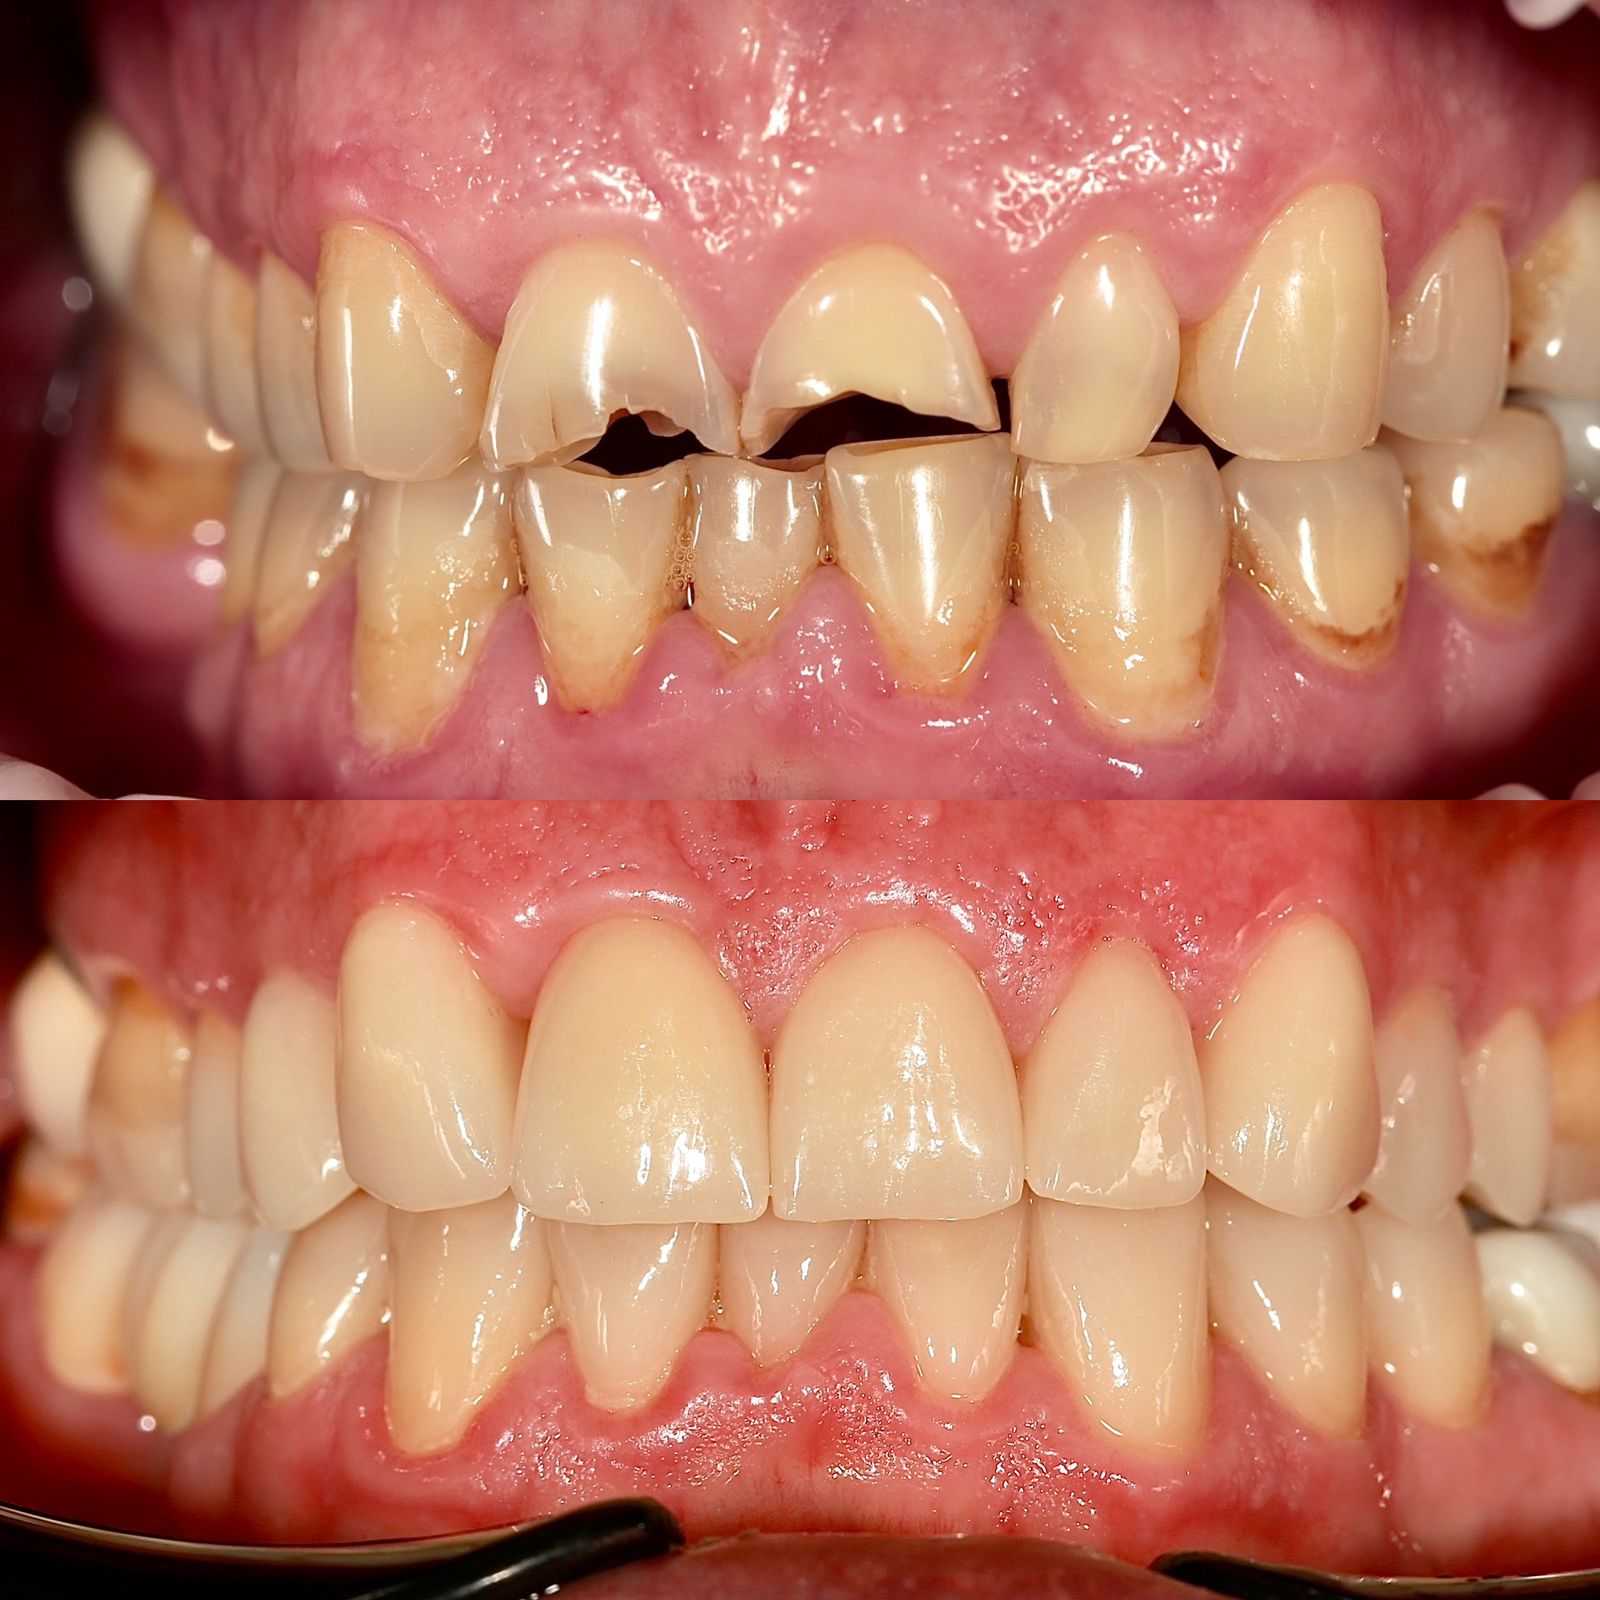

Патологическая стираемость, снижение прикуса . Как помочь?

- Остановить разрушительный процесс.

- Вернуть изначальный уровень высоты коронок.

- Заменить старые протезы, при необходимости.

- Адаптация к новому положению челюсти и ее работе.